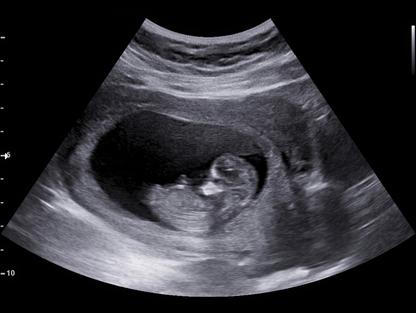

„Jsem ve třetím měsíci a stejně jako s Rozárkou se cítím skvěle a moc si to užívám,“ svěřila se radostně Monika Sommerová, kterou diváci znají z muzikálů jako Bídníci, Čarodějka, Doktor Faust nebo Mamzelle Nitouche. „Za pár týdnů bychom měli vědět pohlaví a jsme napnutí jako strunka. Míša už má tři holčičky, tak by bylo fajn, kdyby to byl chlapeček, taková třešinka na dortu. Ale hlavně ať je to zdravé dítě, to je nejdůležitější,“ dodala pro Super.cz s tím, že už teď se na nový přírůstek těší.